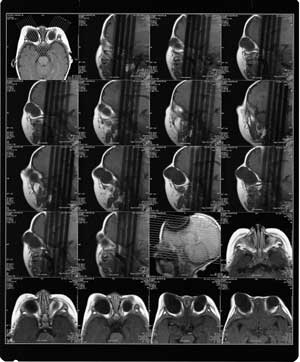

M R I: 双眼球形态失常,内未见晶状体,眼眶内脂肪间隙变小,双眼球外肌及双侧视神经显影。双眼眶扩大,以右侧明显。(见附图MRI-1,MRI-2)